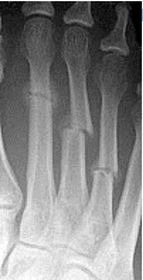

Describe the alignment of metatarsal 2 | There is no angulation nor displacement of the distal segment relative to the proximal segment. |

Describe the alignment of metatarsal 3 | The distal segment is displaced laterally (50% apposition) and angulated medially. |

Describe the alignment of metatarsal 4 | The distal segment is displaced laterally (75% apposition) but there is no apparent angulation. |